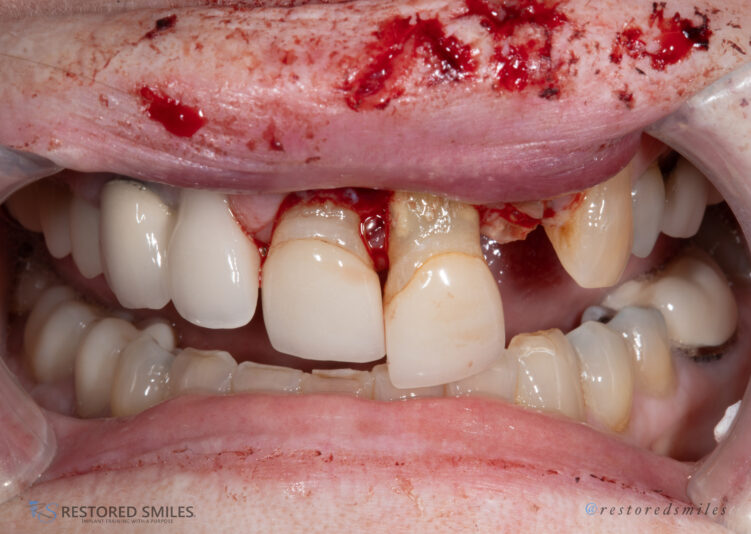

• What in the Trauma is going on? Ok, you all wanted implants and bone grafting so here ya go…

This was a challenging case to say the least, especially when it’s your mother. She fell and fractured 3 of her front teeth amongst other things. A few hours later I had 3 teeth extracted, extracted sockets grafted, ridge augmentation complete, 8…